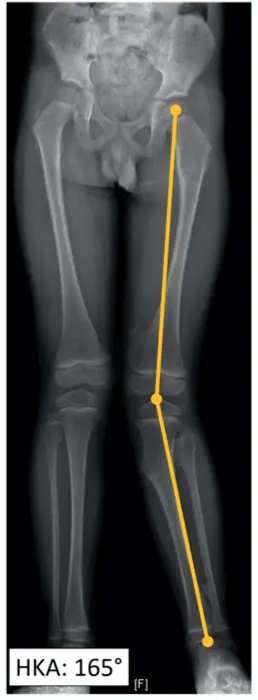

Genu valgum is a frequent deformity encountered in Multiple Hereditary Exostosis (MHE) patients. If left untreated, lower limb deformity leads to poor functional outcomes in adulthood. Our hypothesis was that in some cases, fibular shortening would lead to a lateral epiphysiodesis-like effect on the tibia. We herein report the case of a 6-year-old child with MHE who underwent extraperiosteal resection of the fibula for tibia valga correction. To obtain the lateral release of the calf skeleton, resection included inter-tibio-fibular exostosis along with proximal fibular metaphysis and diaphysis without any osseous procedure on the tibia. Gradual improvement of the valgus deformity occurred during follow-up (HKA from 165 • preop to 178 • at 27-month follow-up). Lateral release of the fibula led to an increase in the fibula/tibia index (from 93% preop to 96% at follow-up). Studying fibular growth in MHE patients could help understand how valgus deformity occurs in these patients. Even if encouraging, this result is just the report of a unique case. Further research and a larger series of patients are required to assess fibular release as a valuable option to treat valgus deformity in MHE.